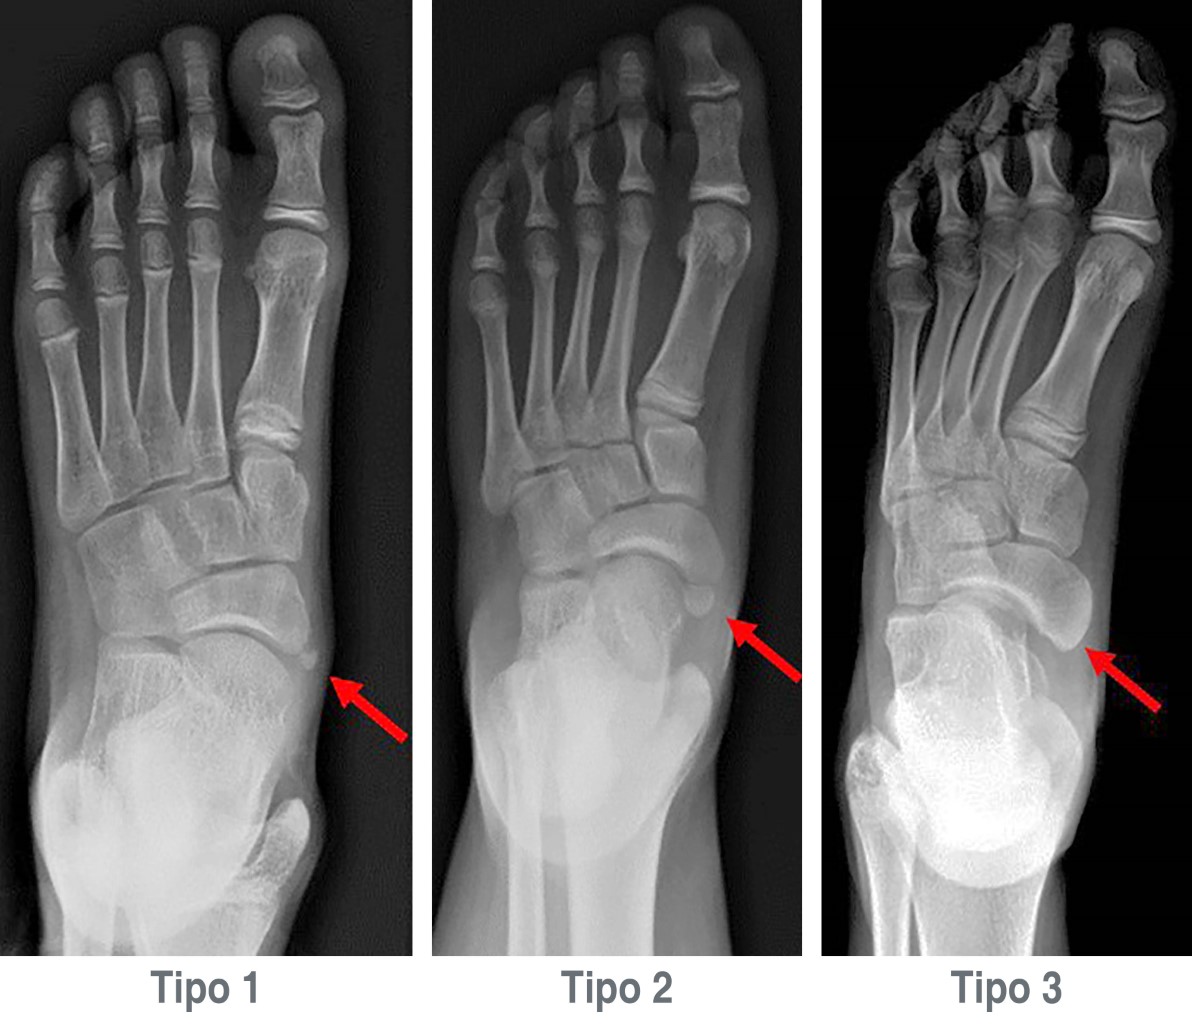

Se obtuvo una muestra total de 87 pacientes (160 pies), los cuales se clasificaron de acuerdo con la morfología que presentaron según la clasificación de Coughlin (Figura 1):

• Tipo 1. Es pequeño, redondo u ovalado.

• Tipo 2. Posee una sincondrosis.

• Tipo 3. Está fusionado con el hueso navicular.4